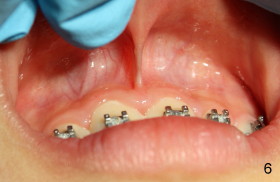

Eight-year-two-month girl has diastema between the maxillary central incisors.  It appears that the upper labial frenum (Fig.3 arrowheads, mirror view) bisects the interdental papilla (Fig.5).  Frenectomy is planned before orthodontic closure of the diastema.  Fig.4 is pre-op X-ray. Five months later, the diastema is closed.  The frenum appears to recede upward (Fig.6).  The bisected papilla seems to fuse (Fig.6,7).  Although the diastema has tendency to relapse when power chains are not used, fixed lingual retainer is planned to prevent the relapse when brackets are to be removed.  It appears that frenectomy is not so highly necessary for this purpose.